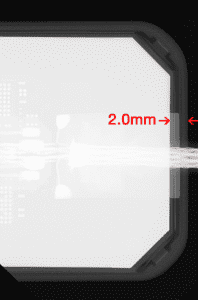

XDR clinicians asked for the dead space to be minimized. By moving the electronics elsewhere, XDR engineers achieved a 2mm mesial dead space, little more than the dead space common with film packets. Figure 1 shows how active imaging area at the mesial edge can help capture of the canine/premolar contact.

Figures 2a through 2d demonstrate how XDR’s imaging area extends further toward the sensor’s mesial edge. XDR has patented this approach under US #9357972B .